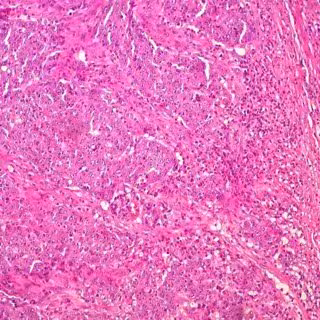

Descubren un circuito celular que aumenta el crecimiento tumoral en cáncer de colon

Cáncer de colon

En él, han logrado identificar un nuevo circuito del microambiente tumoral en el que una proteína secretada por células tumorales en cáncer de colon provoca alteraciones que conducen a un incremento de su crecimiento.

Este trabajo, publicado en la revista Oncogene, ha sido ha sido realizado por Sandra Muñoz-Galván como investigadora principal y liderado por Amancio Carnero, jefe de grupo del CIBERONC e investigador del CSIC, y es de gran importancia para poder conocer la biología de los tumores y lo que determina su evolución. De esta manera, han descubierto que la proteína fosfolipasa D2 (PLD2), la cual se expresa a niveles anormalmente altos en pacientes de cáncer de colon, es secretada por las células tumorales y altera a las células no tumorales del microambiente causando en ellas senescencia.

Esta investigación, que combina estudios con líneas celulares tumorales, bases de datos de pacientes y modelos de animales, abre un camino para el uso de la proteína PLD2 como diana terapéutica para el tratamiento de cáncer de colon y, potencialmente, de otro tipo de tumores. Según han demostrado los investigadores del CIBERONC, las células cancerígenas están en comunicación continua con el microentorno y puede afectar a la evolución del tumor. "Hemos observado que la expresión de PLD2 aumenta en el cáncer colorrectal, lo que induce senescencia en los fibroblastos vecinos y conduce a un crecimiento más rápido del tumor", indica Amancio Carnero.